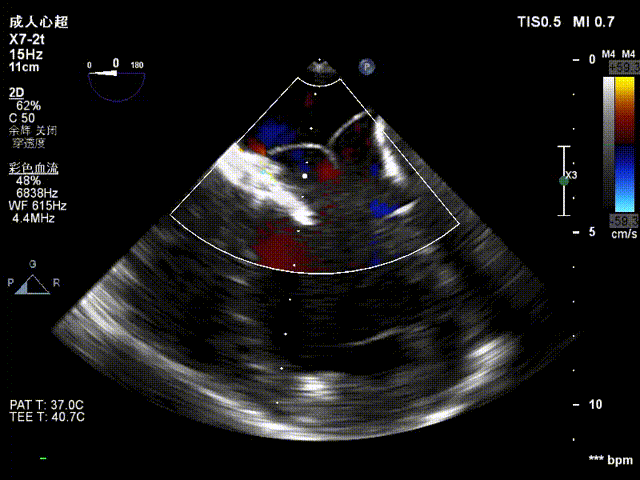

术前二尖瓣反流

手术采用左侧第六肋间微创5cm切口心尖入路,在超声引导下,清晰识别MitraFix®输送系统准确跨瓣,并将人工瓣膜准确释放于二尖瓣瓣环,瓣膜释放后支架贴合牢固,术后无反流,二尖瓣前向血流通畅、跨瓣压差1mmHg,左心室流出道通畅,流出道血流速度为1 m/s. 后顺利撤出输送系统,关闭心尖切口,手术顺利结束。